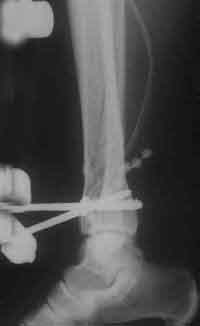

Montage der wichtigen dritten Carbonstange

postoperativ (seitlich)